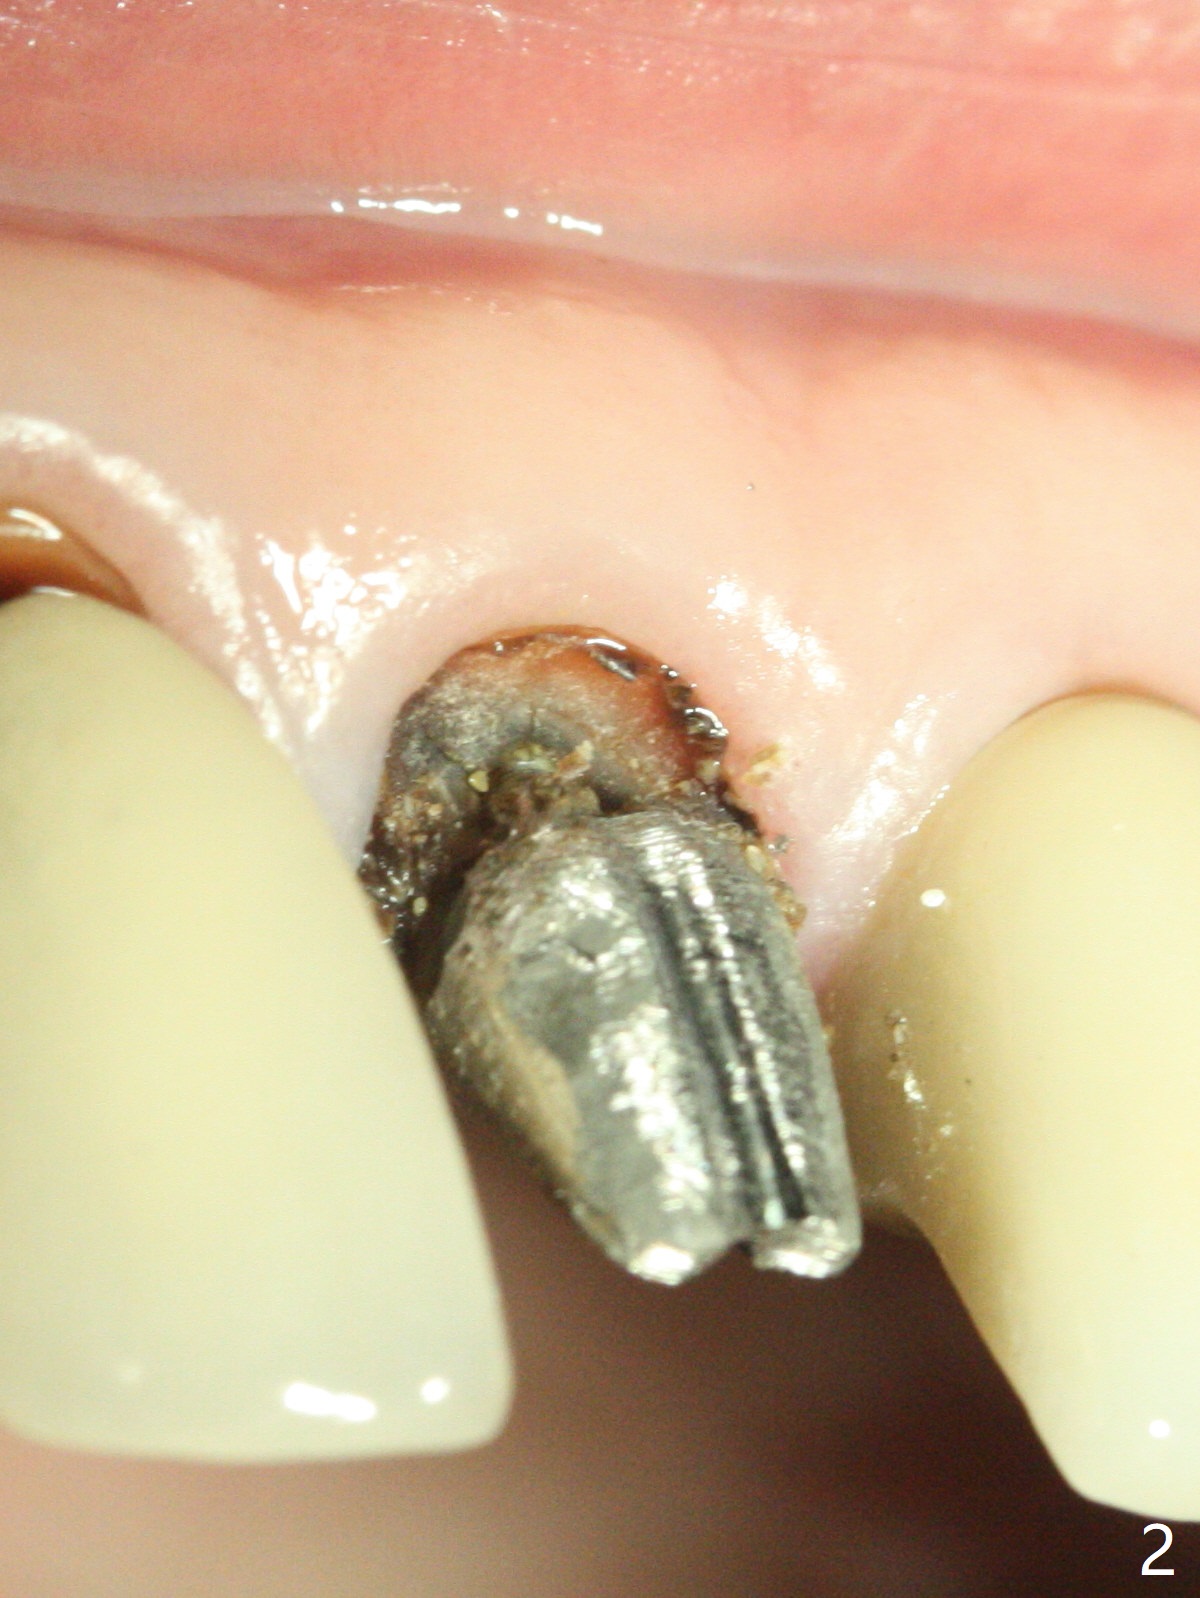

A 66-year-old man returns to clinic for #8 crown redo because of marginal leakage (Fig.1 *). After crown and caries removal, the tooth requires crown lengthening or basically non salvageable (Fig.2,3). For untold reasons, gingivectomy is performed with Waterlase without topical or local anesthesia. Hemostasis is excellent for impression, although there is wide spread of tissue debris from laser (Fig.4 >). The gingiva heals 4 weeks (Fig.5) and 6 weeks (Fig.6) postop.